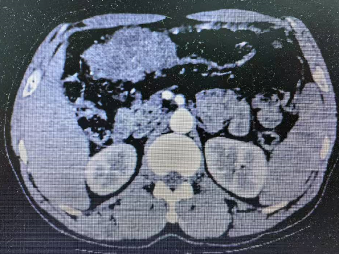

老年患者郑某某,男,60多岁,以“上腹部胀满不适1月余” 之主诉于2023年12月入住老年普外科大明宫院区(普外科四病区)王志东教授团队组。入院行胃镜检查显示胃窦癌,胃潴留,慢性萎缩性胃炎,反流性食管炎。病理活检示胃窦粘膜中-低分化腺癌(图三所示)。上腹部增强CT回报示胃窦、横结肠及其间隙内近9cm肿块型肿瘤,结肠侵犯可能,如图一所示。术前临床分期:cT4bN2M0(IIIb期)也就是通常称呼的局部晚期胃癌。将术前检查评估情况告知家属后,听到局部晚期胃癌的噩耗,家属近乎绝望。王志东教授团队耐心的和病人及家属沟通后,联合肿瘤科、影像科、老年医学科等进行了肿瘤多学科诊疗和老年病多学科诊疗(MDT)后,对该患者实施了6个周期的化疗和PD-1免疫治疗,期间患者适应性良好,未出现严重不良反应。

2023年12月CT结果 腹腔可见巨块型肿瘤